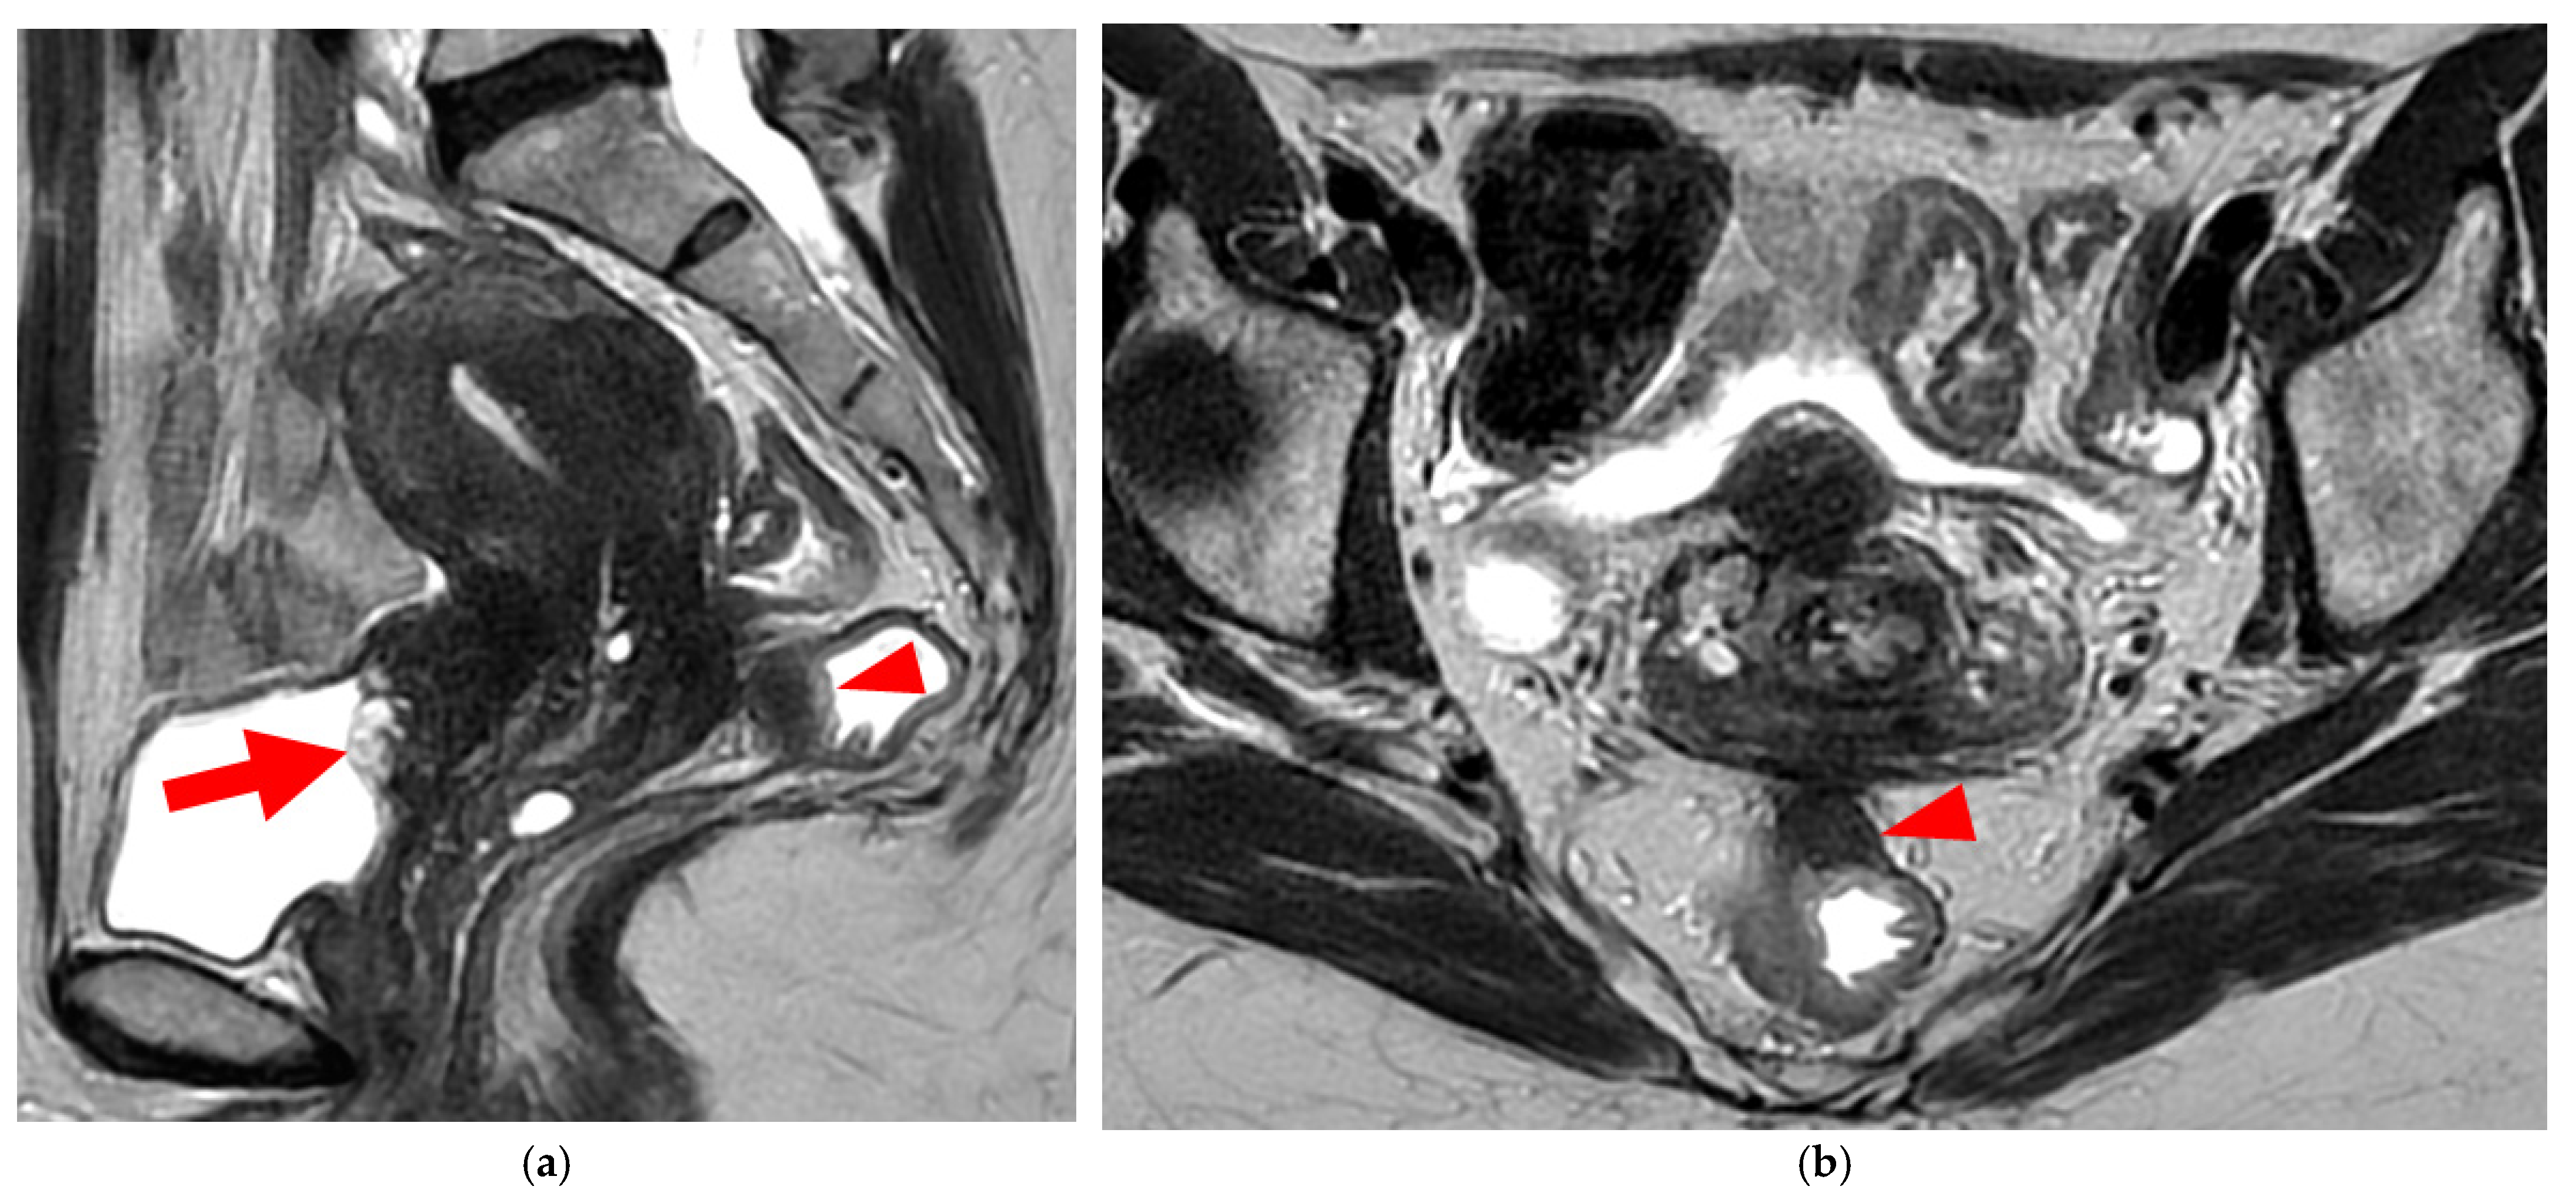

Figure 6. Pelvic MRI scans of two patients with HTD type 5A USLs. (a,b) Sagittal T2WI: nodularity with regular margins (arrows) within the right USL (arrowheads).

A type 5A USL (Figure 6) is nodular with a smooth contour.